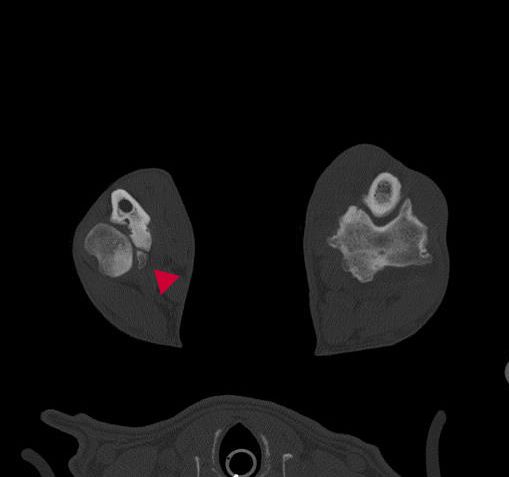

Die Computertomographie ist als Schnittbildverfahren geeignet, dreidimensionale Bilder der zu untersuchenden Körperregionen zu erstellen. Sie ist eine bildgebende diagnostische Methode, die auf der Abschwächung von Röntgenstrahlen basiert, die von Detektoren erfasst und in relative Dichtewerte (Hounsfieldeinheiten) umgerechnet werden. Sie wird oft dann eingesetzt, wenn durch die klinische Untersuchung, konventionelles Röntgen oder Ultraschall keine Diagnose gestellt werden kann.

Zur Untersuchung ist eine kurze Vollnarkose notwendig. Durch die Gabe jodhaltiger Kontrastmittel kann der Gewebekontrast noch einmal deutlich verbessert werden. Eine solche zusätzliche Untersuchung kommt im Falle der Tumordiagnostik häufig zum Einsatz.

Wir verwenden ein Spiral-CT der Firma Siemens für computertomographische Untersuchungen. Die Untersuchungszeiten bei diesem modernen Gerät sind sehr kurz, so dass eine längere Narkose vermieden werden kann.